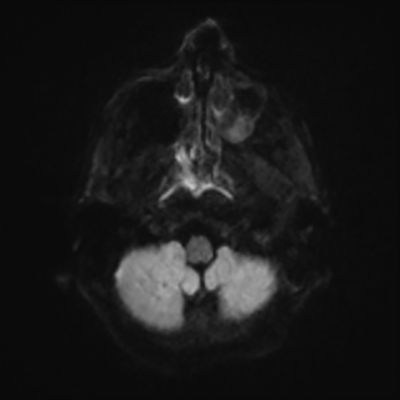

MRI brain (DWI)

You can clearly see diffuse cortical and basal ganglia diffusion restriction, and that of his deep cerebellar nuclei as well. The right occipital lobe abnormalities are a little more prominent, but then you remember that he is known to have had a right occipital stroke weeks ago.